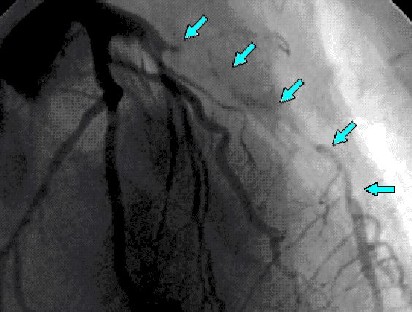

Caso C-3

Coronariografía

Se demuestra lesión larga de arteria descendente anterior, sin otras lesiones significativas. Se decide implante de stent.